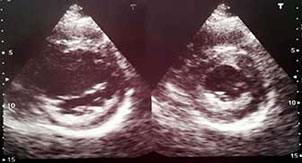

Paciente masculino de 29 años con antecedentes de dos episodios de pérdida de conocimiento que fueron atribuidos a convulsiones. Ingresa por presentar un nuevo episodio de pérdida de conocimiento con recuperación ad integrum. Se encontraba con una presión arterial de 155/110 mm Hg y una frecuencia cardíaca de 78 lpm. El examen neurológico inicial no mostraba signos de foco agudo. En el examen cardiológico se auscultó un soplo sistólico regurgitante mitral, el resto del examen físico del paciente era normal. El electrocardiograma evidenciaba ritmo sinusal, frecuencia cardíaca de 78 lpm y signos de hipertrofia ventricular izquierda con ondas T negativas profundas simulando una miocardiopatía hipertrófica (figura 1). La radiografía de tórax era normal. Realizamos un ecocardiograma Doppler que mostró diámetros ventriculares normales, aurícula derecha con dilatación leve, dilatación acentuada de la aurícula izquierda y una fracción de eyección del ventrículo izquierdo de 66%. Observamos un aumento de la ecogenicidad del endocardio en los segmentos inferolateral mediobasal e inferior mediobasal (figura 2). La válvula mitral se encontraba levemente engrosada con apertura normal, un área de 1.96 cm2, e insuficiencia moderada. En el flujograma mitral se observó un patrón de relajación prolongada.